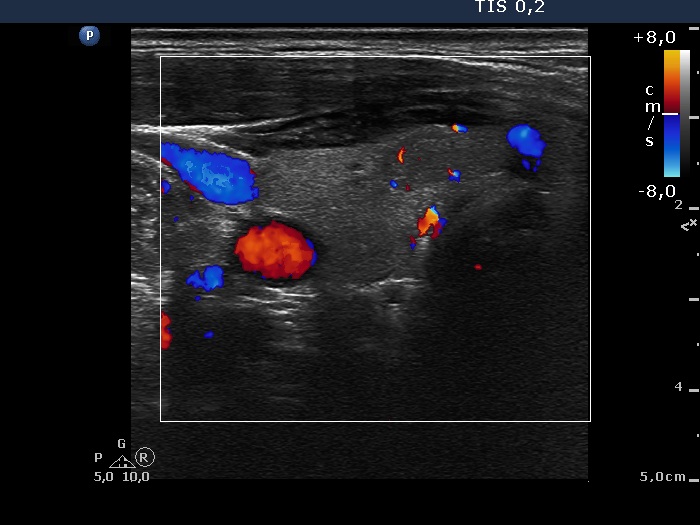

Ultrasonography: the thyroids were echonormal. There was a small hypoechogenic lesion in the ventral part of the right lobe, while a large hyperechogenic nodule presenting a halo sign and perinodular blood flow in the left thyroid. The size of the nodule increased from 25x19x27 mm to 30x27x33 mm (width, depth, length, respectively).